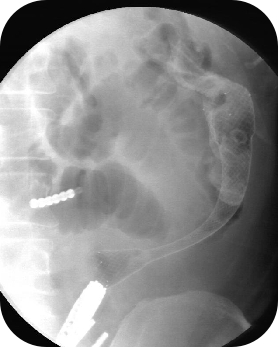

使用网状支架将肠道撑开前后对比图

史立军指出,国内外众多学者开展多种术中近端肠道减压和灌洗方法,但仍有手术时间较长,污染腹腔,肠道电解质丢失扰乱机体内环境等弊病。采用金属支架作为肠腔内支撑治疗结直肠恶性梗阻,即在肠道狭窄的部位放置一个网状支架将肠道撑开,使狭窄或阻塞部位重新恢复通畅,可作为结直肠癌恶性梗阻的永久或暂时性治疗,并为择期手术创造条件。